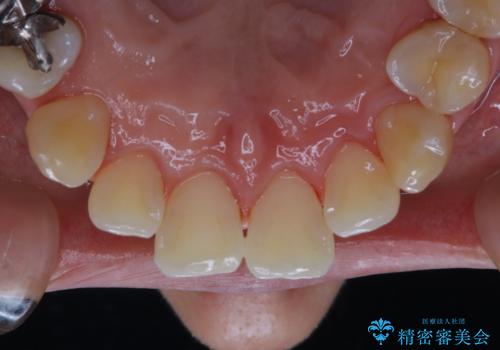

バイオフィルムが除去されると、ご自身本来の歯の表面になります。PMTCをすることで口臭予防にもなり、定期的に行うことが大切です。

- 歯を白くする目的の施術ではありません